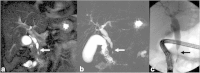

Malignancies of the biliary tract include cholangiocarcinoma, gallbladder cancers and carcinoma of the ampulla of Vater. Biliary tract adenocarcinomas are the second most common primary hepatobiliary cancer. Due to their slow growing nature, non-specific and late symptomatology, these malignancies are often diagnosed in advanced stages with poor prognosis. Apart from incidental discovery of gall bladder carcinoma upon cholecystectomy, early stage biliary tract cancers are now detected with computed tomography (CT) and magnetic resonance imaging (MRI) with magnetic resonance cholangiopancreatography (MRCP). Accurate characterization and staging of these indolent cancers will determine outcome as majority of the patients' are inoperable at the time of presentation. Ultrasound is useful for initial evaluation of the biliary tract and gallbladder masses and in determining the next suitable modality for further evaluation. Multimodality imaging plays an integral role in the management of the biliary tract malignancies. The imaging techniques most useful are MRI with MRCP, endoscopic retrograde cholangiopancreatography (ERCP), endoscopic ultrasound (EUS) and positron emission tomography (PET). In this review we will discuss epidemiology and the role of imaging in detection, characterization and management of the biliary tract malignancies under the three broad categories of cholangiocarcinomas (intra- and extrahepatic), gallbladder cancers and ampullary carcinomas.